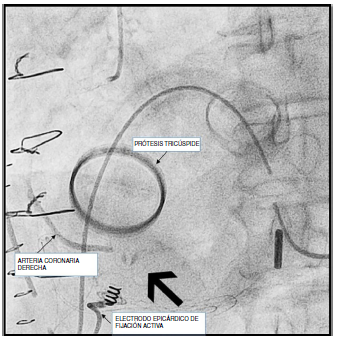

Se presenta el caso de una mujer de 68 años con antecedente personal de sustitución valvular mitral por prótesis mecánica en el año 2000 y colocación de stent convencional en la CD proximal en el año 2007. Como factores de riesgo cardiovascular presentaba diabetes mellitus, hipertensión arterial y dislipidemia. Se encontraba en fibrilación auricular (FA) lenta a 40 latidos por minuto. Estaba en seguimiento por insuficiencia tricuspídea severa. En el ecocardiograma la VT presentaba velos restrictivos, de aspecto reumático, además se observaba VD dilatado con función sistólica levemente deprimida y ventrículo izquierdo (VI) no dilatado con fracción de eyección (FE) del 47% e hipoquinesia moderada del segmento medio-basal de la cara septal. Se encontraba en clase funcional (CF) III/IV de la New York Heart Association (NYHA). La coronariografía preoperatoria mostraba dominancia derecha sin lesiones coronarias significativas y sin reestenosis del stent. Se decide intervenir quirúrgicamente realizándose una sustitución valvular tricúspide (SVT) por prótesis mecánica ATS nº 33 e implante de electrodo de marcapasos epicárdico definitivo de manera profiláctica, en cara diafragmática de VD, dados su antecedente de FA lenta y mayor incidencia de bloqueo AV con la SVT4,7. En el postoperatorio inmediato presentó ascenso persistente del segmento ST en cara inferior. Se decidió implante de balón de contrapulsación intraaórtico y ecocardiograma urgente donde se observó disfunción ventricular global con aquinesia de cara inferior. Tras aproximadamente una hora en la Unidad de Cuidados Intensivos, se hizo coronariografía urgente que mostró imagen de angulación y deformidad a nivel distal de la CD no presente en la coronariografía prequirúrgica, que sugería tracción externa del vaso, probablemente en relación con la sutura quirúrgica (fig. 1). Se cruzó dicha zona con guía Pilot 50 y con guía BMW, se predilató con balón de 1,2 y 2 mm y se implantó stent farmacoactivo de 3x20 mm recuperando flujo distal TIMI (thrombolysis in myocardial infarction) 3 tanto en la rama descendente posterior como en la rama posterolateral (fig. 2). Tras la intervención percutánea se normalizó el segmento ST. Respecto a los marcadores de daño miocárdico los valores máximos de CPK (creatina fosfoquinasa), CPK-MB (creatina fosfoquinasa fracción MB) y troponina T hs se alcanzaron a las 12 horas del ingreso en la Unidad de Cuidados Intensivos y fueron 1.781 U/l, 175,4 ng/ml y 13.415 ng/l respectivamente. El ecocardiograma postoperatorio objetivó un VI no dilatado con FE del 40% e hipoquinesia del septo, inferior y anterior; VD no dilatado con disfunción sistólica leve-moderada y prótesis tricúspide normofuncionante. El resto de la estancia hospitalaria transcurrió sin incidencias y la paciente fue dada de alta a los 17 días postoperatorios sin secuelas y en proceso de rehabilitación. En la revisión postoperatoria a los tres meses de la intervención quirúrgica, se encontraba en clase funcional II/IV de la NYHA y en el ecocardiograma de control se observó VI no dilatado con FE del 39% con hipoquinesia marcada en cara inferior e inferolateral, VD dilatado con función sistólica severamente deprimida, prótesis mecánicas en posición tricúspidea y mitral normofuncionantes y signos indirectos de hipertensión pulmonar.